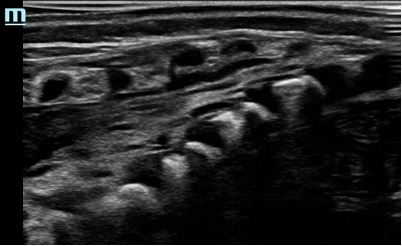

- At birth, the ossification centres of the spine are at an early stage of development; it is therefore possible to obtain excellent spinal images in neonates. With age and increasing ossification, the US window to the spine diminishes (the ossification is complete at 21 years old)

Caudal in a neonate